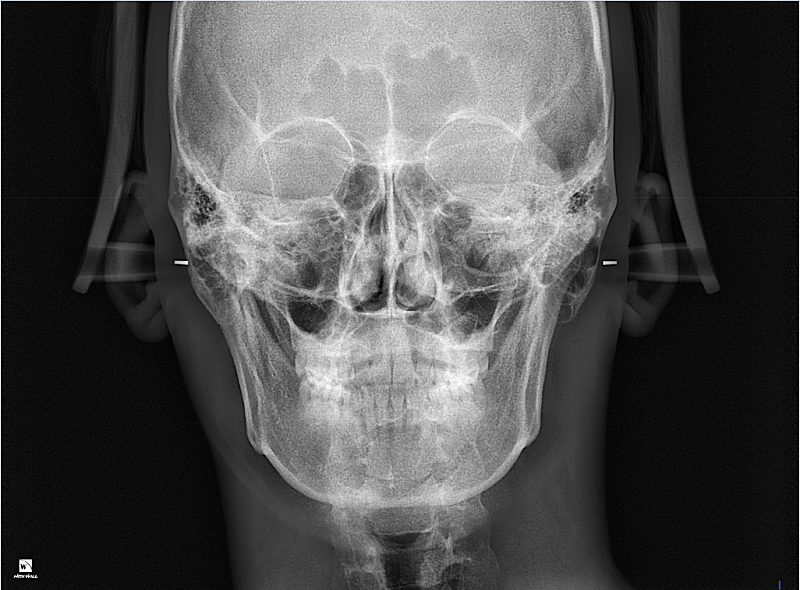

2. 입다물때 비대칭 별로 티안나는것 같은데 입벌리고 아랫치아보면 치아가 한쪽으로 기운느낌이 드는데

턱관절문제 일까요? 치아가 기운 문제일까요? 양쪽 턱뼈 길이차이 문제일까요?

2. 현재로서는 골격적 비대칭일 가능성이 더 큽니다. 즉 교정을 이용해서 이를 해결하기는 쉽지 않으며 보통 골격이 틀어진 경우 교정을 하더라도 한계가 있습니다.